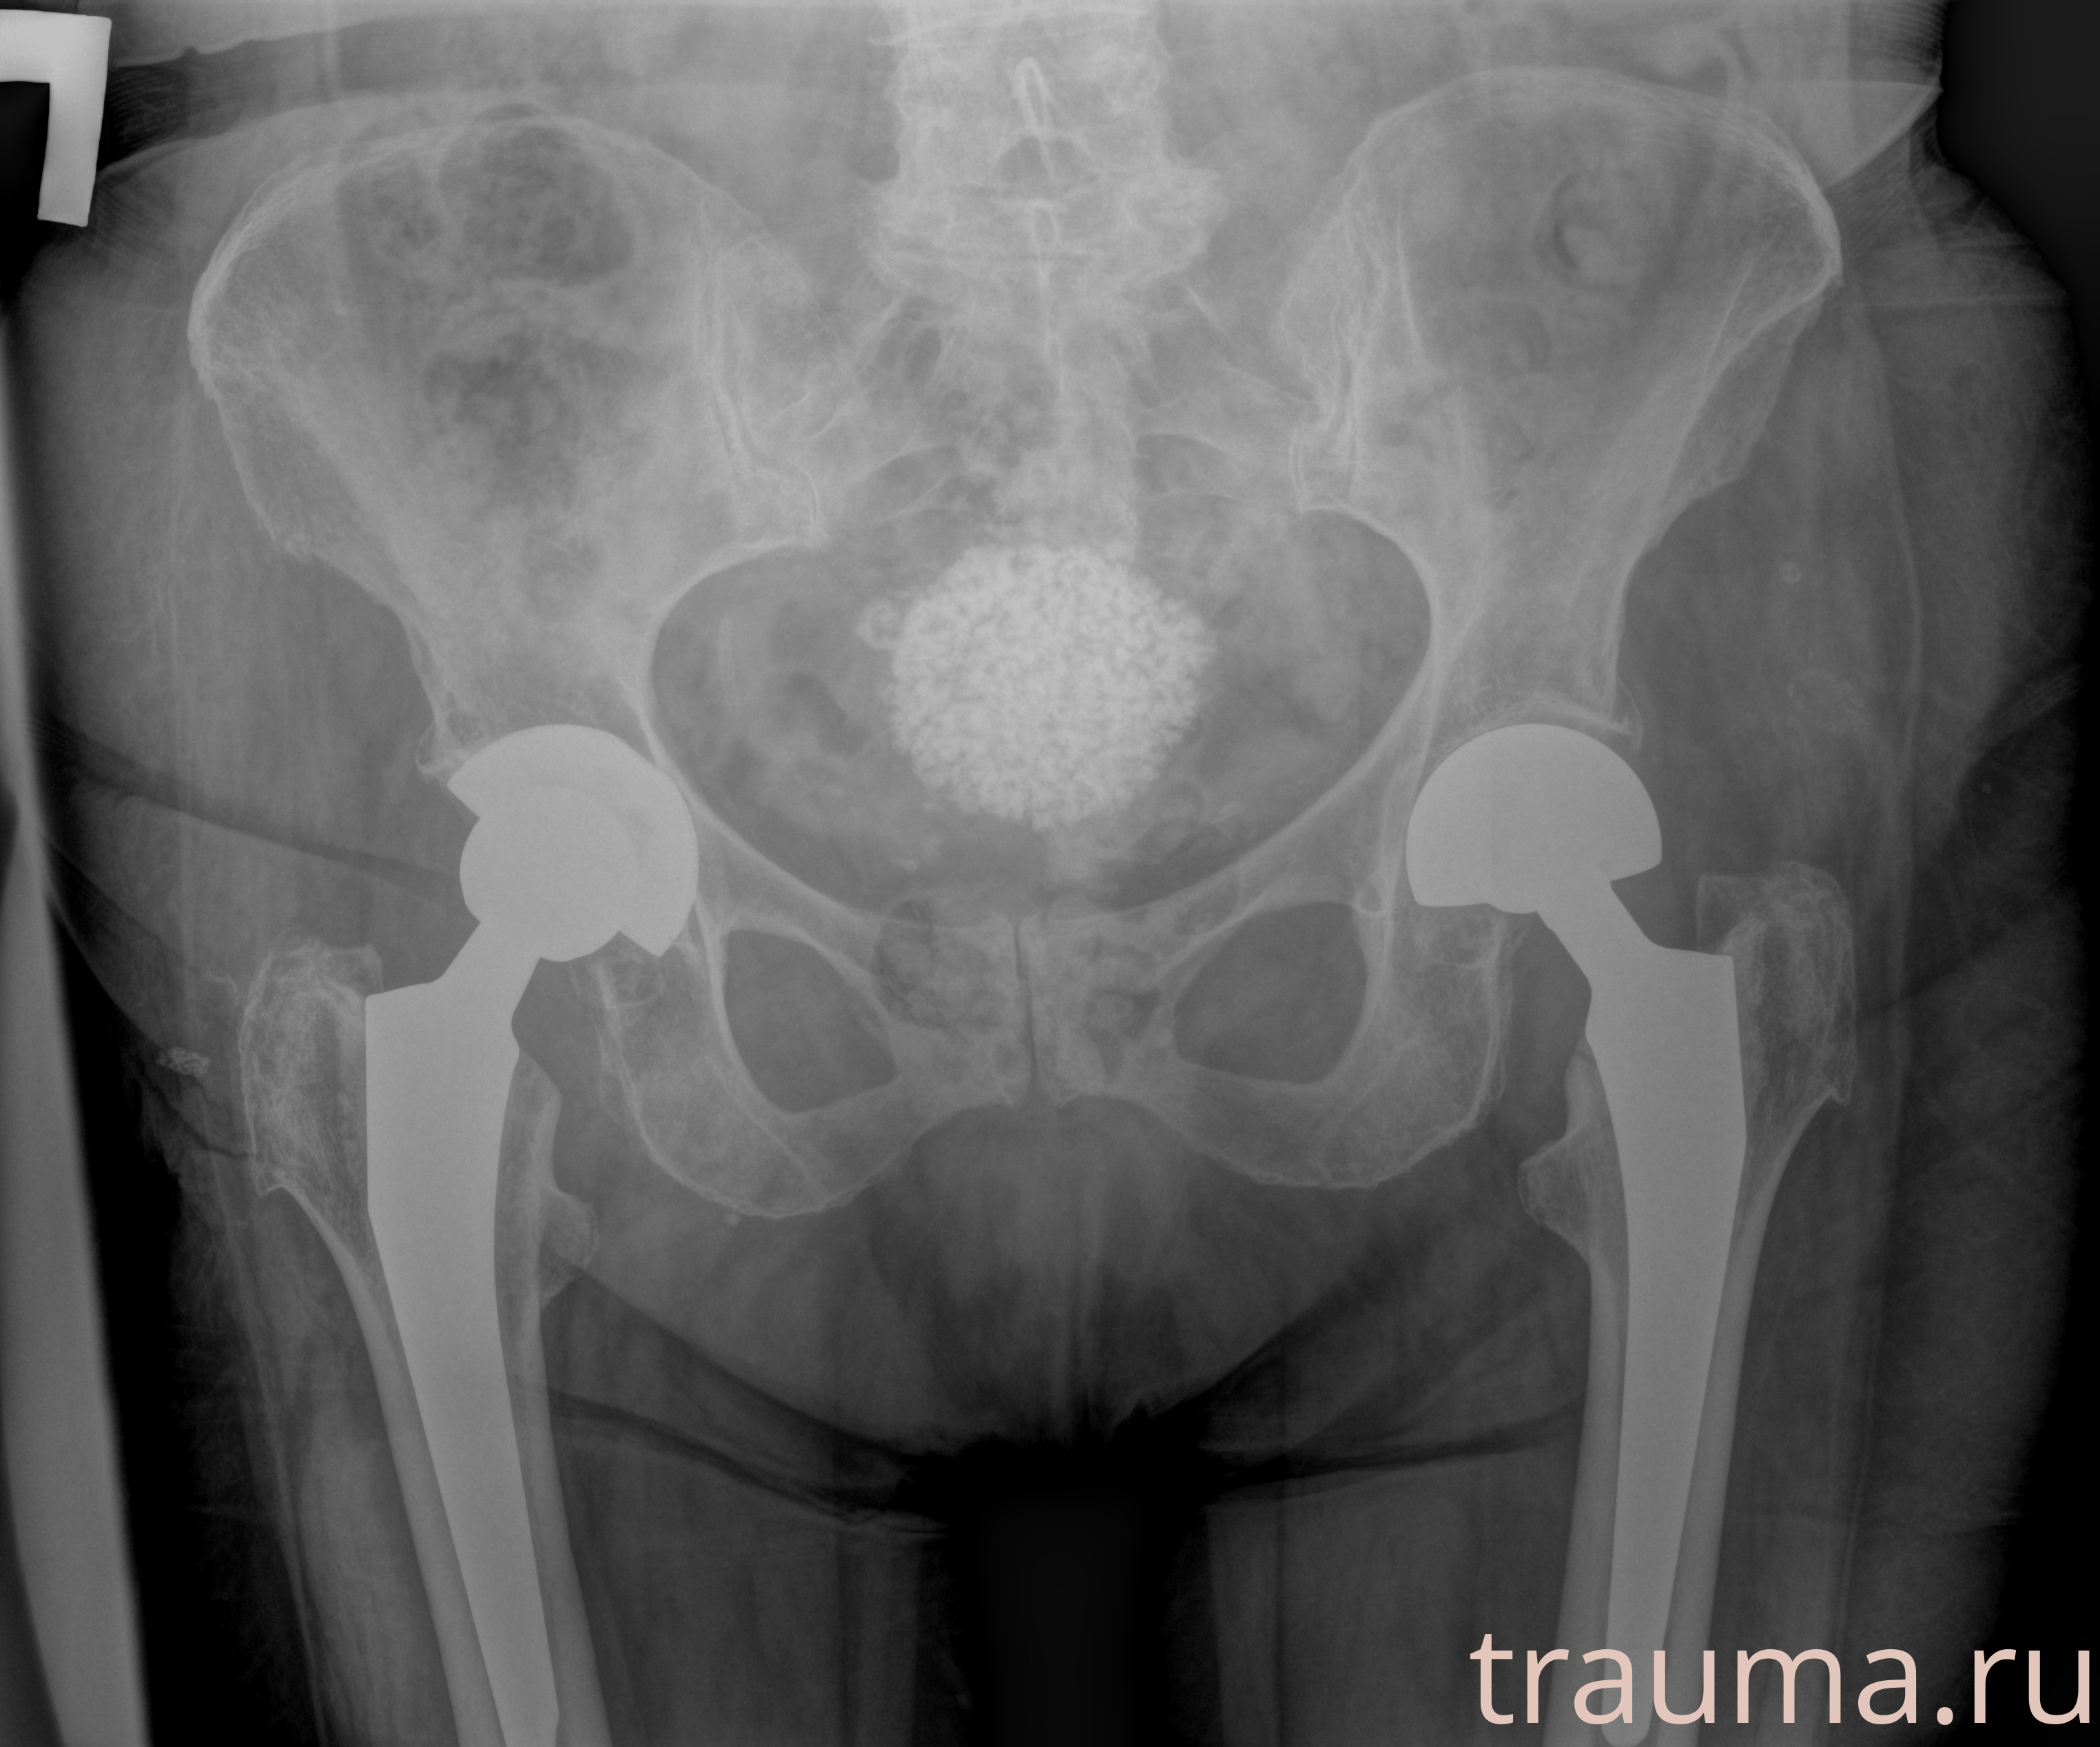

Рентгенограммы

Рентген на дому: по вашему адресу приезжает врач-рентгенолог, травматолог-ортопед с мобильным рентгеновским аппаратом, проводит диагностику травмы или заболевания, делает необходимые рентгенограммы, дает рекомендации по дальнейшему лечению. Получить качественные снимки в домашних условиях возможно благодаря уникальной методике, разработанной МосРентген Центром для института  Склифосовского

при переломе шейки бедра и пневмонии от компании МосРентген Центр - партнера Института имени Склифосовского